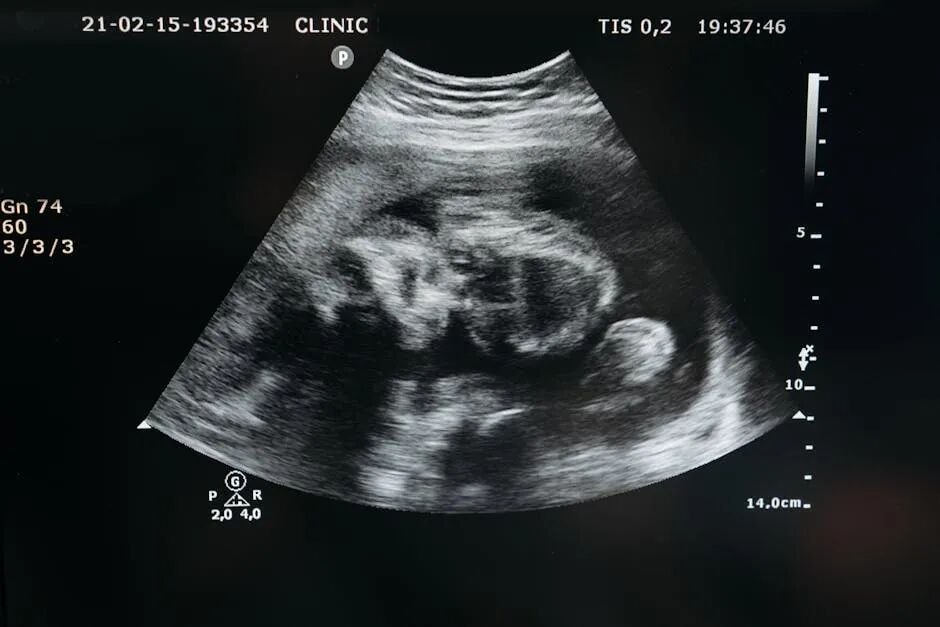

试管婴儿是通过在体外实验室中将卵子和精子结合,培养出胚胎,然后将胚胎移植到母体子宫内进行发育。

试管婴儿的过程 1、卵巢刺激 在这个过程中,医生会使用注射药物来刺激卵巢产生更多的卵子。这可能导致一些不适,如轻微的腹胀和不适感,但通常不会引起剧烈的疼痛。 2、卵子采集 这是试管婴儿过程中最有可能引起一些不适的步骤。这是通过穿刺术或超声引导下的细针,从卵巢中取出卵子。在卵子采集过程中,一般使用局部麻醉或轻度镇静,以确保您不会感受到明显的疼痛。 3、受精和胚胎培养 4、胚胎移植 胚胎移植通常是一个简单而快速的过程,不需要使用麻醉。医生将直接使用细管或导管将胚胎置入子宫内。 选择泰国,试管成功率高达75% 泰国作为试管婴儿的高成功率目的地,它拥有先进的医疗技术和专业的医疗团队,提供世界一流的试管婴儿治疗。 泰国的医疗设施和医生经验丰富,成功率非常高。此外,通过选择泰国作为试管婴儿目的地,您还可以享受美丽的自然环境和友好的旅游经验。 如果您是第一次去泰国,也完全不用担心人生地不熟。 思普乐提供一站式试管助孕服务,包含机票协助预订、接送机、住宿、翻译、诊所预约、检查报告分析等一系列服务。 ✦ • ✦ ✦ 左右滑动,查看更多 ✦ *以上图片:思普乐目前提供的泰国接送机、住宿等服务 试管婴儿的过程通常不会引起剧烈的疼痛,但一些轻微的不适或不舒服可能是正常的。重要的是,与您的医生和专业团队进行沟通,让他们了解您的感受并采取适当的行动。